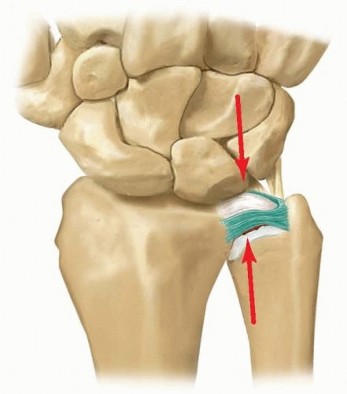

The biomechanical principles governing the wrist were elegantly quantified by Palmer and Werner. In a normal wrist with ulnar-zero variance, the radius absorbs approximately 80% of the axial load, while the ulna absorbs the remaining 20%. However, this load distribution is highly dynamic and exquisitely sensitive to changes in ulnar variance. A mere 2.5 mm increase in ulnar length (ulnar-plus variance) shifts the ulnar load bearing from 20% to a staggering 42%.

This pathological load shift is the fundamental driver of ulnar abutment syndrome. The repetitive impaction of the ulnar head against the proximal pole of the lunate and the triquetrum leads to a predictable sequence of degenerative changes. Initially, the central articular disc of the TFCC undergoes attritional thinning and subsequent perforation (Palmer Type IIA and IIB). As the abutment continues, chondromalacia develops on the ulnar head and the proximal ulnar aspect of the lunate (Palmer Type IIC).

If left unaddressed, this relentless mechanical conflict progresses to attenuation and eventual rupture of the lunotriquetral (LT) interosseous ligament (Palmer Type IID), culminating in advanced ulnocarpal and DRUJ arthritis (Palmer Type IIE). By performing an arthroscopic ulnar shortening (wafer procedure), we are mechanically uncoupling the ulnocarpal joint. Resecting 2 to 3 mm of the distal ulna beneath the TFCC tear effectively normalizes the load transmission, alleviating the impaction forces and providing profound, durable pain relief.

With the TFCC débrided and the ulnar head exposed, we proceed to the arthroscopic wafer procedure. This is the most technically demanding portion of the operation. The objective is to resect 2 to 3 mm of the distal ulnar dome, decorticating the articular cartilage and the underlying subchondral bone, to achieve an ulnar-minus variance.